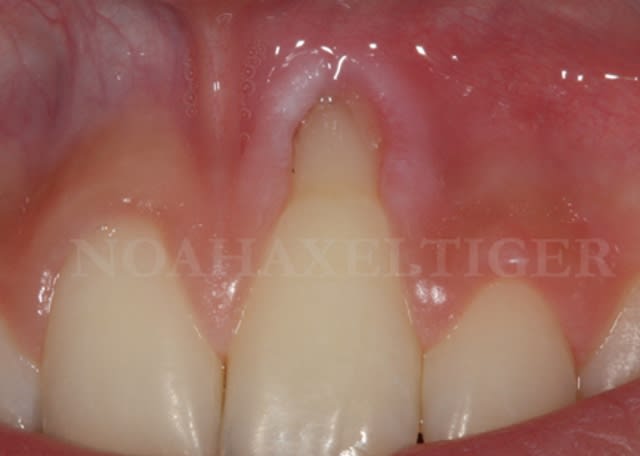

Img 8465 fqhxid - Eugenol

.

Initial ctkv65 - Eugenol

Lit receveur loll9i - Eugenol

Mise en place du greffon conjonctif ejn6xx - Eugenol

Sutures e7ixmz - Eugenol

Zone de prelevement palatin wngjgr - Eugenol